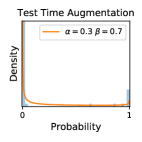

5.1 Distribution of Uncertainty Scores

Distribution of Uncertainty Scores Across Different Severity Levels As explained in Section 3, each uncertainty metric essentially defines an order/ranking among the data points. We conducted an analysis to better understand what data will be assigned high uncertainty under a particular uncertainty metric . Picking out the highest ranked data points (), we calculated the ratio of data points from each SL. Figure 4 summarizes the results as box plots for the Kaggle-DR and the Messidor-2 datasets; additional detailed statistics can be found in Table S.1 in the supplementary materials. From the plot and table, SL1 & SL2 examples account for a higher proportion among the top-ranked uncertain examples across the three ensemble methods. This finding matches our intuition that incipient disease examples (SL1 & SL2) are more likely to be considered uncertain by ensemble methods due to their ambiguity.

In contrast, the MC-dropout method showed the worst overall performance among the three, as it can be seen from the high ratios of SL0 examples among the uncertain negatives in Figure 4. The histograms in Figure 2 provides another perspective to look into the phenomenon, where a decent proportion of MC-dropout model’s predictions on SL0 inputs entailed low confidence (far from 0 or 1), which from another angle explained why MC-dropout was less specific in terms of lower FNP; many no-DR inputs (i.e. SL0) were erroneously assigned high uncertainty by MC-dropout models.

It is still an open question why the evaluated MC-dropout networks signaled relatively high uncertainty on SL0 & SL3 & SL4 data that are less likely to be ambiguous. We conjecture that much of the “uncertainty” indicated by disagreement among test-time dropout samples actually reflects the stochastic nature of dropout networks rather than the real decision uncertainty associated with the data. It is worth noting that the MC-dropout model we evaluated was not weak per se; they all achieved above Area Under Curve (AUC) scores on test sets. The weakness of individual test-time samples (which explains their low-confidence predictions on SL0 & SL3 & SL4) might have been hidden when they are aggregated into an ensemble—a well-known advantage of ensemble learning. Our results suggested that the uncertainty information given by implicit ensemble methods such as MC-dropout and TTA might not be as reliable as that from explicit ensemble approaches (e.g., stacking ensembles). Similar findings on MC-dropout can be found in some previous papers [1].